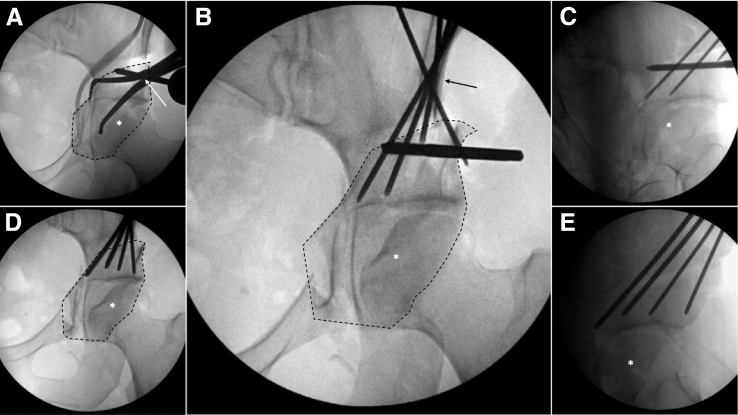

Fig 6.

Left hip intraoperative fluoroscopic images demonstrating: (A) Shanz pin and Weber clamp, marked with an arrow in place, mobilizing the fragment (outlined); (B) anteroposterior (AP) pelvis 2.4-mm K wires in place, provisionally fixing the fragment (outlined) in its new orientation; (C) a false profile view demonstrating the 2.4-mm K wires provisionally fixing the fragment in place; (D) AP, with the fragment outlined, and (E) false-profile views demonstrating screws in place (two 3.5-mm screws anteriorly and two 4.5-mm screws posteriorly). The femoral head is marked in each of the images (A-E) with an asterisk.